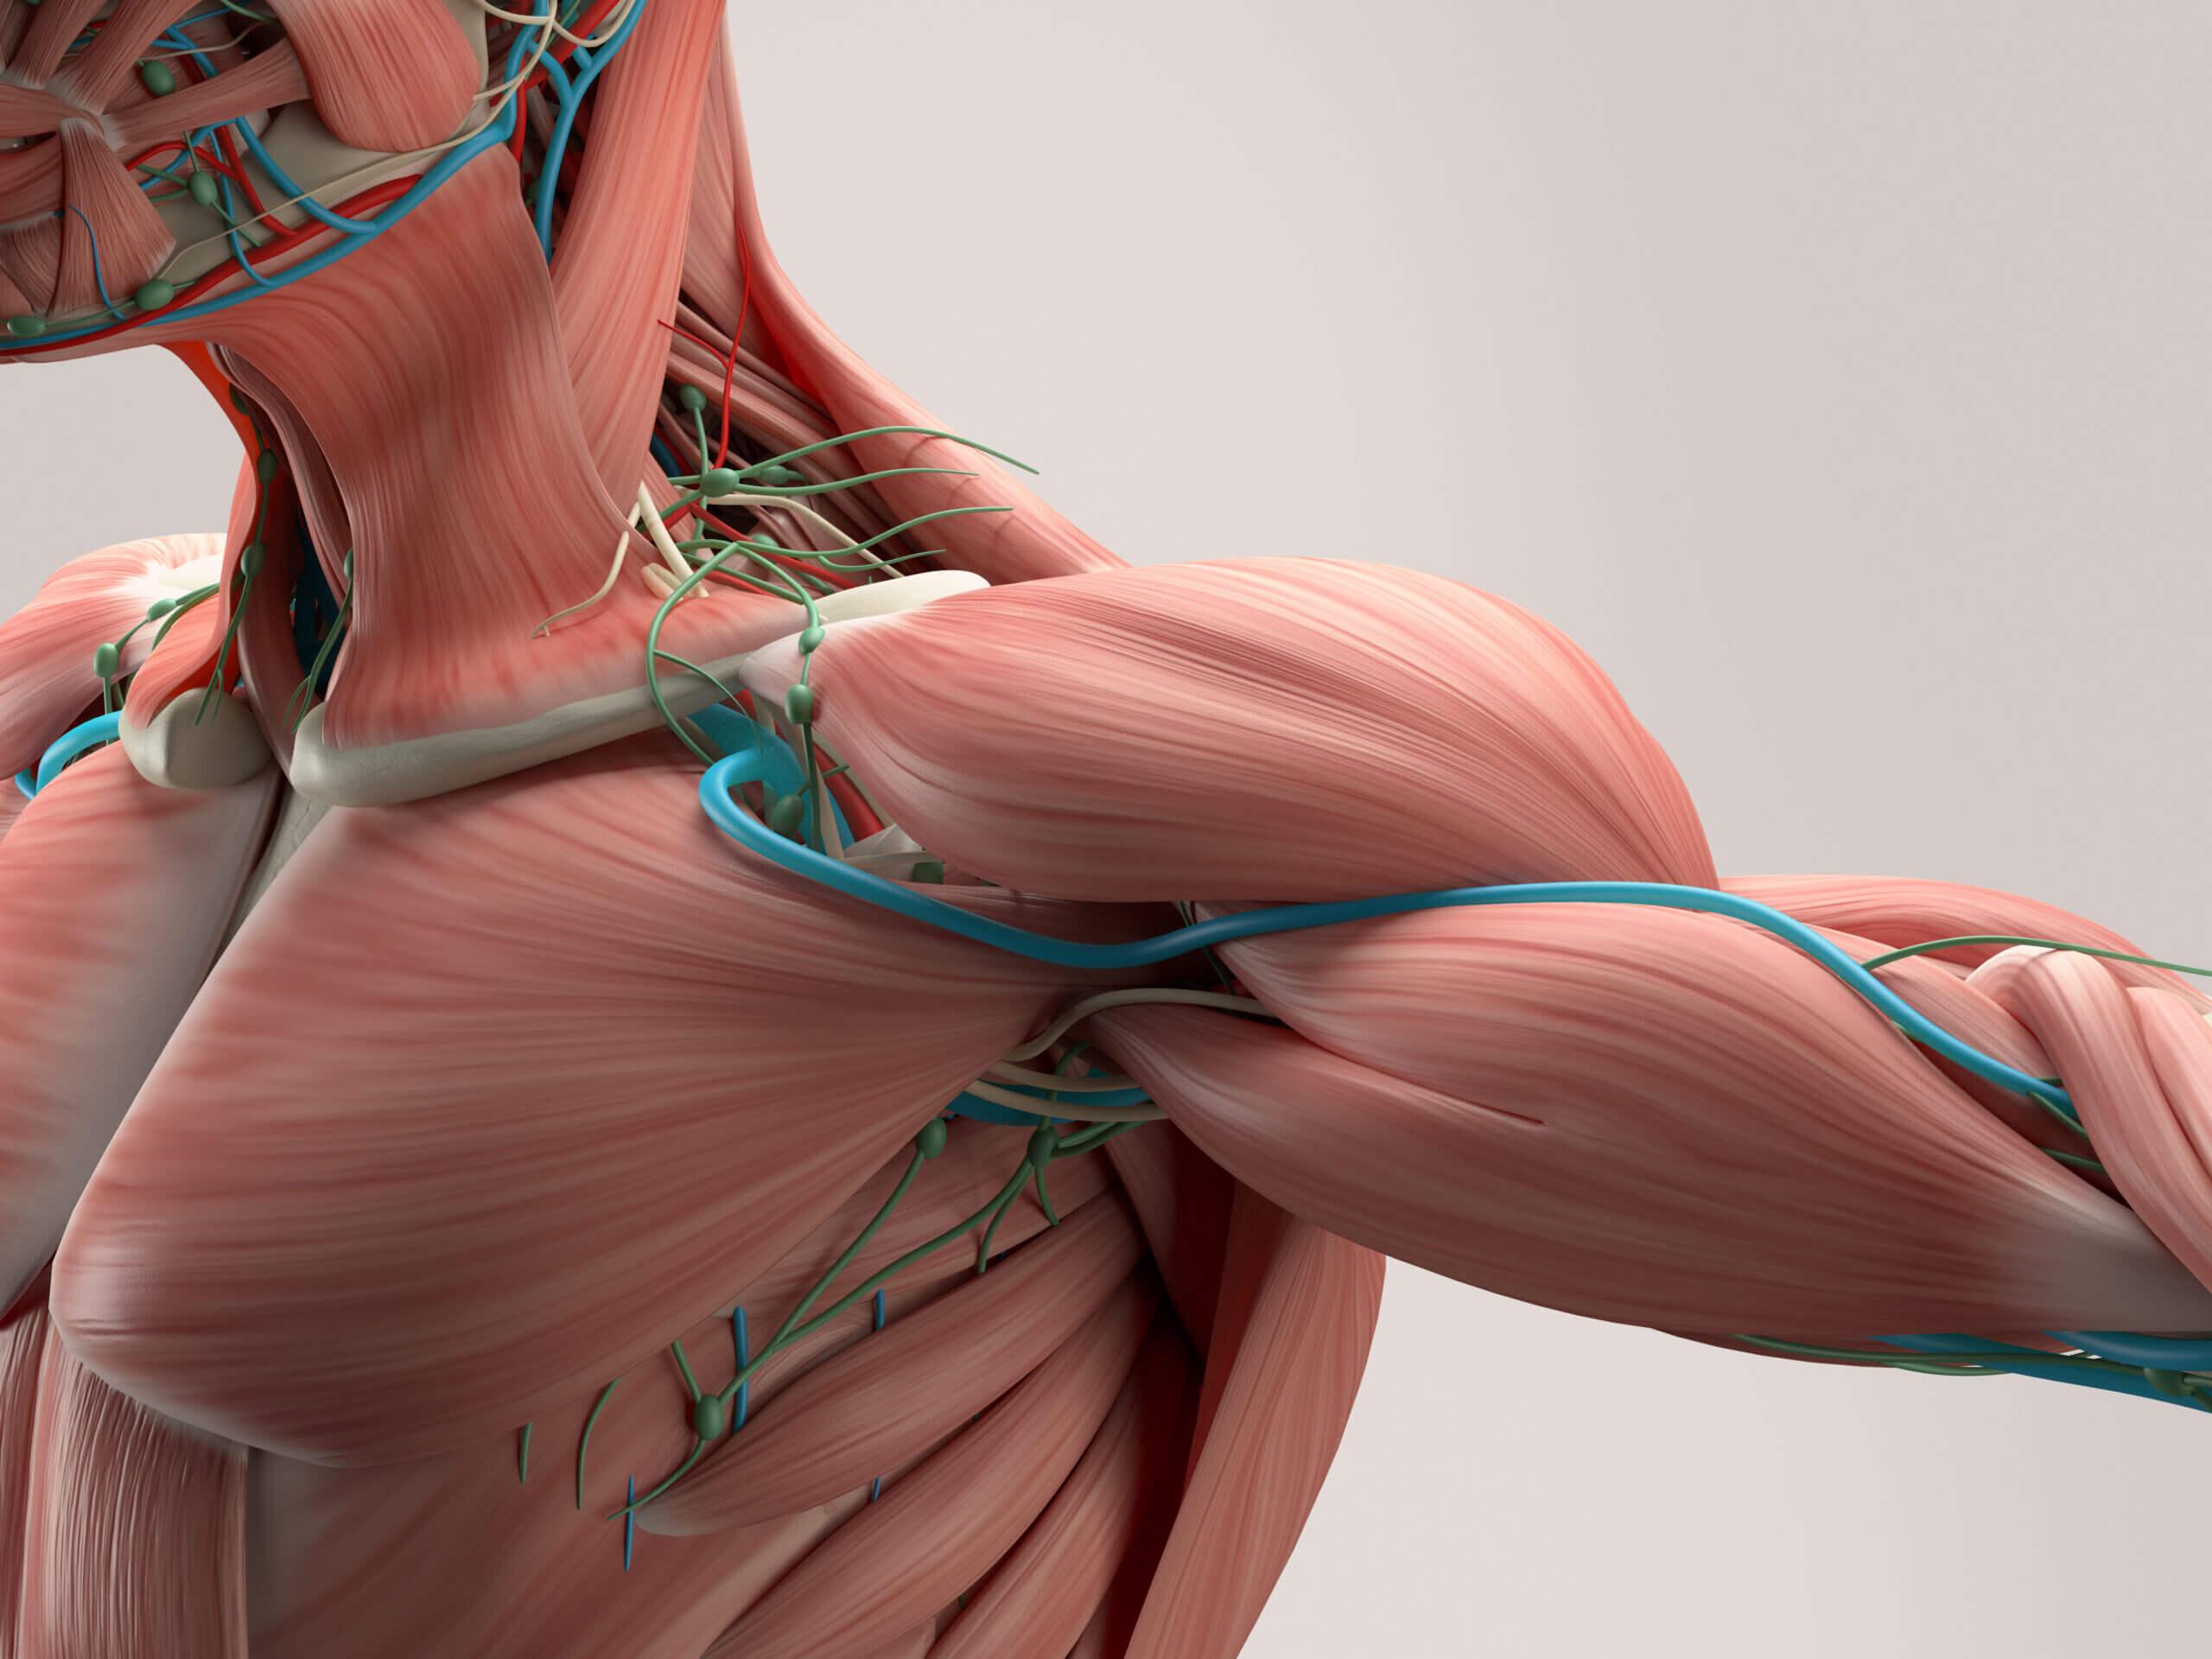

قیمت: 77٬000 تومان - دسته بندی فایل: پاورپوینتآسیب های استخوانی مفصلی و عضلانی

فروش ویژه پاورپوینت حرفه ای آسیب های استخوانی مفصلی و عضلانی با تخفیف استثنایی فقط 69 هزار تومان تعداد اسلاید: 21

قیمت: 68٬000 تومان - دسته بندی فایل: پاورپوینتپاورپوینت ساختمان و کار عضله

فروش ویژه پاورپوینت حرفه ای ساختمان و کار عضله با تخفیف استثنایی فقط 49 هزار تومان تعداد اسلاید: 78 اسلاید